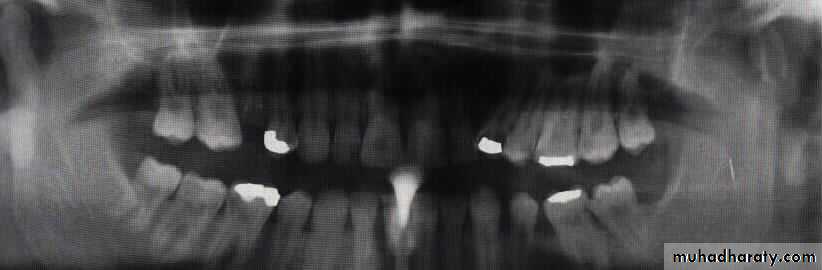

Radiographic evaluation:

Plain radiographOPG

Lateral oblique

PA mandible

AP mandible (reverse Townes)

Lower occlusal

CT scan

3-D CT imaging